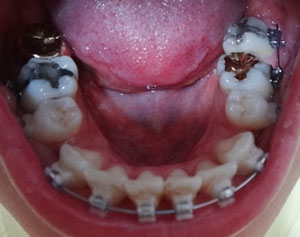

상악 왼쪽 오른쪽 어금니에 부착되어진 오라픽스 장치에 스프링 조절을 조금 더 해주었어요.

돌출된 치아를 밀어 넣기 위해서 발치공간 확보가 조금 더 필요한 상태인가봐요.

하악에 파워체인 제거하고 와이어 교체했어요~

확실히 하악은 발치공간이 많이 닫힌거 같아요.

파워체인은 부착하지 않았고, 와이어만 교체해서 부착했어요.